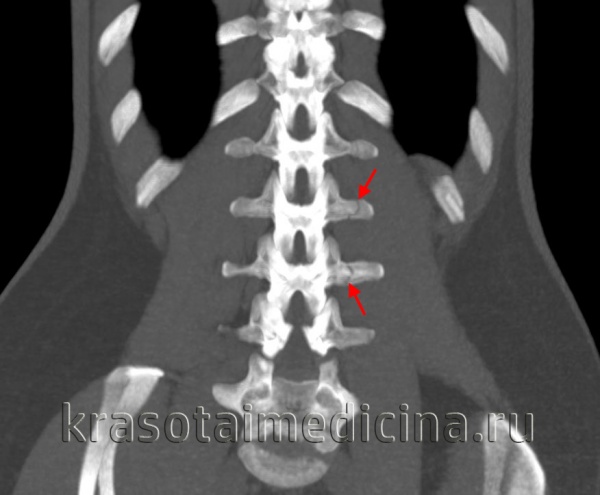

(Слева) КТ, сагиттальный срез: оскольчатый взрывной перелом тела L4 позвонка со смещением фрагмента кпереди и выраженным смещением одного из фрагментов кзади.

(Справа) На Т1 -ВИ отмечается снижение интенсивности сигнала тела L4 позвонка на фоне его перелома. Смещенные кзади фрагменты сдавливают вентральную поверхность дурального мешка, имеет место значительных размеров эпидуральная гематома. Таким образом, выраженная компрессия дурального мешка связана со смещением фрагментов в спинномозговой канал и эпидуральной гематомой.

(Слева) КТ, сагиттальный срез: взрывной перелом тела L1 позвонка со смещением задней покровной пластинки в спинномозговой канал. Линия перелома продолжается на заднюю сосудистую бороздку. Нормальная сосудистая бороздка отличается от перелома ровными контурами и характерной локализацией.

(Справа) На фронтальном КТ-срезе этого же пациента виден вертикальный перелом межсуставной части дуги. Это характерное для компрессионного механизма травмы повреждение, отличающееся от горизонтального перелома задних элементов при флексионно-дистракционных повреждениях.